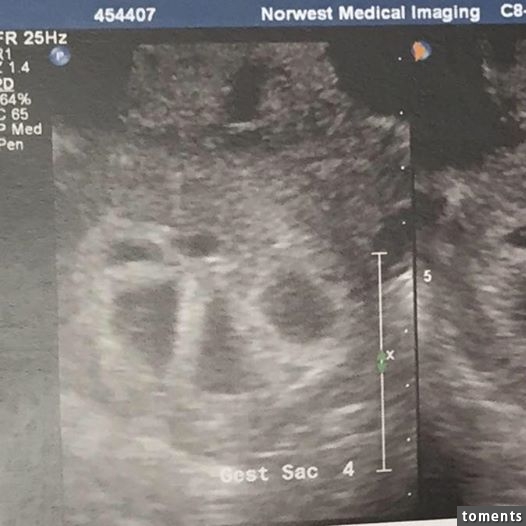

▼她第一次照超音波時,竟發現她懷了五胞胎!

Kimberly說:「當時醫生超驚訝!他開始看著超音波照數,一個、兩個、三個、四個、五個!!!當時我不敢相信,想說是不是聽錯了?五個???因為太震驚我的腿開始顫抖起來,然後醫生就告訴我懷了五胞胎!!!」